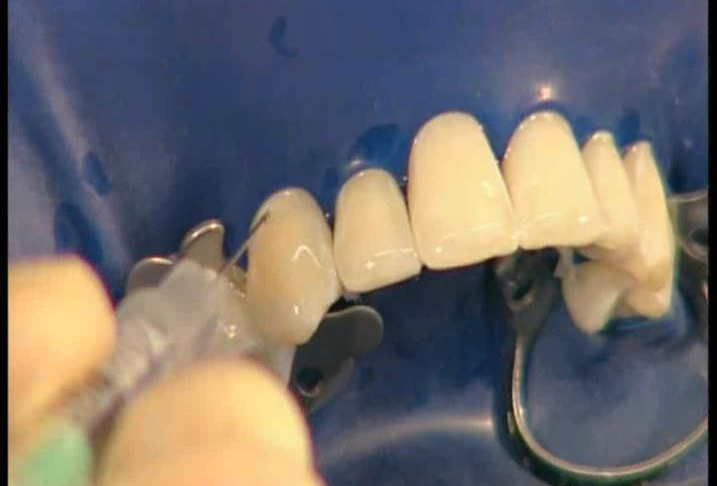

2、牙面清洁后,橡皮障隔湿

dmg口腔材料怎么使用DMG-Icon专利之渗透树脂(内含操作视频)_https://www.jmylbn.com_新闻资讯_第7张